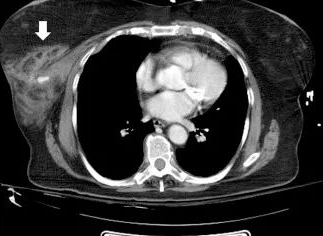

In the medical paper A Systematic Review of Female Seat Belt Trauma: A New Diagnostic and Management Classification, 31% of patients reported experiencing pain, swelling, open wounds, or local bleeding immediately after a road traffic accident. 69% of patients experienced delayed onset of symptoms, ranging from 3 weeks to 5 years, ranging from a visible mass at the trauma site to worsening fissure deformities, and most late reports were diagnosed with fat necrosis.